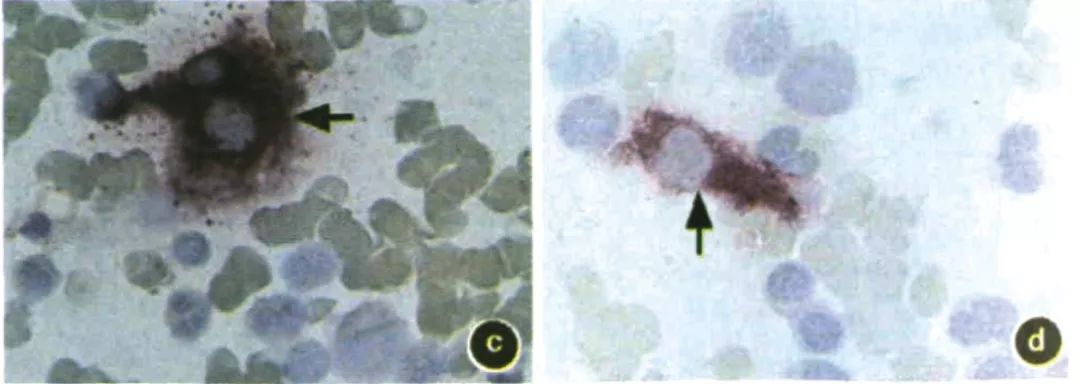

◆染色效果

图a~d: 骨髓涂片

a~d图箭头所示为骨髓基质细胞胞质染为紫红色,胞核不着色,而其他细胞均无此染色特征(固紫B盐染色x1000)